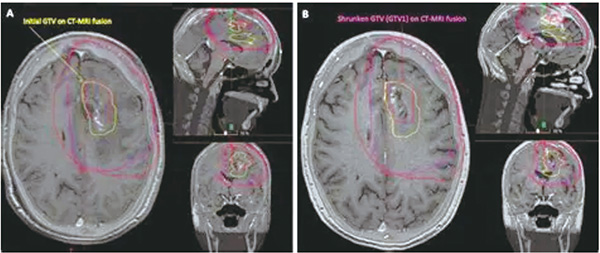

FET-PET在诊断复发性胶质母细胞瘤方面的特异性CE-T1MRI。为了评估基于FET-PET的靶体积勾画与CE-T1MRI相比,是否能改善拟再次放疗的复发性胶质母细胞瘤患者的结局,该项在德国15个放射肿瘤中心进行的、多中心、开放标签、平行分组随机研究(GLIAA/NOA-10 ARO2013-01)纳入≥18岁的、卡氏评分≥60%的、大体下WHO分级为4级(1~6 cm)的、复发性胶质母细胞瘤患者,等比分予基于FET-PET或CE-T1MRI的靶体积勾画,随后再次放疗(39 Gy/13 f),并按照首次放疗时间、既往化疗、肿瘤直径、MGMT状态和计划的化疗进行分层。

在按照方案集内,FET-PET组和CE-T1MRI组各有患者98例和97例。删失者的中位随访时间为12.2个月(IQR:6.6~20.7个月)。FET-PET组和CE-T1MRI组的中位PFS分别为4.0个月(95%CI 3.7~5.2个月)和4.9个月(95%CI 3.7~6.0个月;分层对数秩检验,P=0.98;校正风险比为1.14,95%CI 0.85~1.52,P=0.39);6例删失者的中位随访时间为4.1个月。